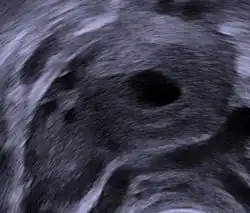

Le corps jaune (corpus luteum) est une formation temporaire[1], à l'intérieur de l'ovaire, qui résulte de la transformation du follicule de De Graaf (follicule mûr ou encore déhiscent) après expulsion de l'ovocyte lors de l'ovulation.

Ce corps jaune, qui se forme durant la phase lutéale (la troisième[2] étape du cycle ovarien), a pour fonction de sécréter de la progestérone (provenant du cholestérol sanguin) sous contrôle d'une hormone hypophysaire, la LH. La progestérone a pour rôle de maintenir la muqueuse utérine destinée à accueillir l'embryon lors de la nidation. En cas de non-fécondation de l'ovule, le corps jaune dégénère, se flétrit, entraînant avec lui une diminution de la sécrétion de la progestérone et finalement l'apparition des règles correspondant au début d'un nouveau cycle. Si l'embryon se fixe, le corps jaune va se maintenir et produire de la progestérone pendant le début de la grossesse, sous contrôle de la gonadotrophine chorionique humaine (hCG). Il disparaît vers le 3e ou 4e mois lorsque le placenta acquiert une autonomie suffisante.